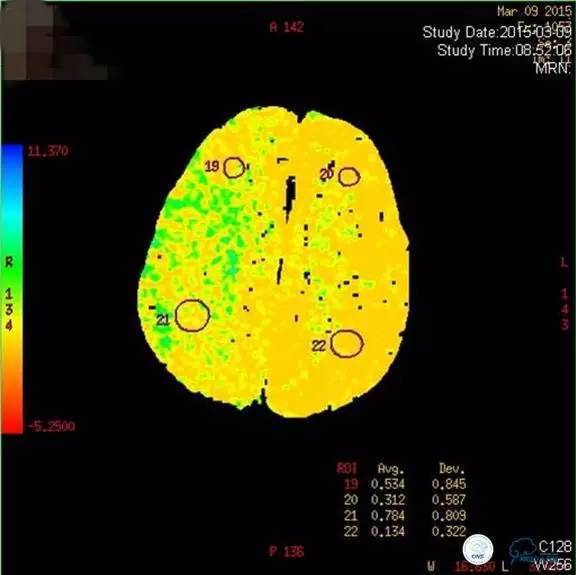

core-clilnical明显不匹配,是介入开通的合适患者。